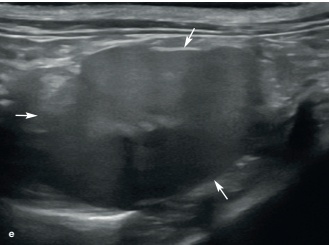

비장의 국소적 병변은 실질내 편만하게 에코성의 변화가 있는 것 보다 쉽게 발견됩니다(그림 8). 국소적 혹은 여러 국소적인 비장 결절들은 개와 마찬가지로 고양이에서도 흔하지 않습니다. 발생 시에는 정상 비장의 실질보다 등에코성 내지 저에코성을 보입니다.

(c) 11세 중성화된 수컷 고양이에서 림프종(lymphoma)으로 인해 이질적인 비장 종양(화살표)이 관찰됨. 복부 내 림프절 비대와 소량의 복수도 확인됨.

(d) 12세 중성화된 암컷 고양이에서 암종증(carcinomatosis)과 관련된 비장 꼬리 부분에 크고 잘 경계된 종양(측정 캘리퍼 사이)이 존재. 종양은 나머지 비장 실질에 비해 등에코성을 보이며, 편심적으로 위치한 이질적인 무에코 영역 또한 있음. 3개월 전 시행한 초음파 검사에서는 비장이 정상으로 확인되었으며, 전이성 또는 가능성 있는 원발성 신생물성 비장 질환이 가장 가능성 높은 감별 진단으로 고려됨.